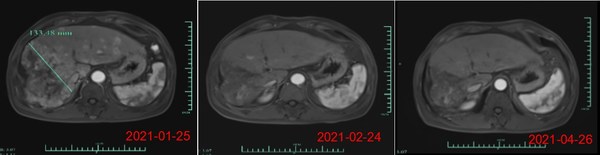

其中,受试者007的PR缓解时间超过6个月,肿瘤体积减少超过80%。截止日前该患者的缓解周期已超过8个月,仍在持续随访中。另一名疗效显著的受试者012是一位弥漫浸润性非常晚期的肝癌患者,曾接受过 12次以上的TACE治疗,在放疗及靶向治疗无效后加入本研究。回输28天后MRI结果显示最大肿瘤直径从133mm减少至9mm,缩小超过90%。目前,该受试者在回输3个月后评估,MRI扫描结果显示此肿瘤几乎消失。相应地,回输28天后其AFP (甲胎蛋白,诊断原发性肝癌特异性的肿瘤标志物)水平从>80000降至1148.9ng/ml,回输3个月后降至746.7ng/ml (其正常值是在0-40ng/ml以内),展示了Ori-CAR-001在晚期肝癌治疗的显著有效性。